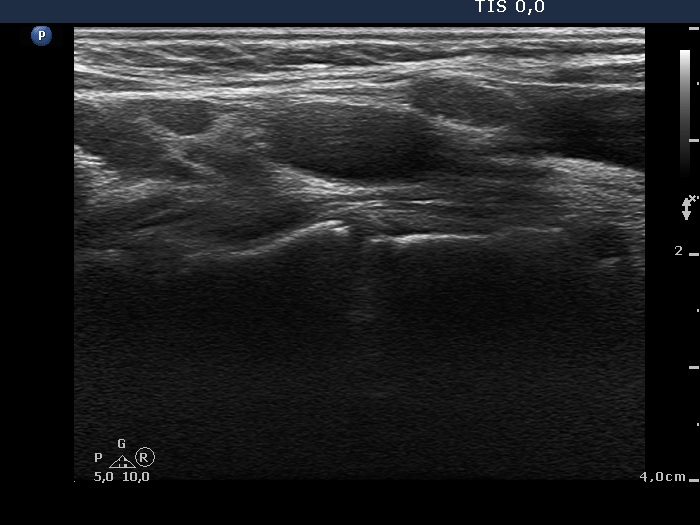

Ultrasonography: We could not find thyroid parenchyma. A small lymph node was present lateral to the left thyroid bed. The hilum was absent.